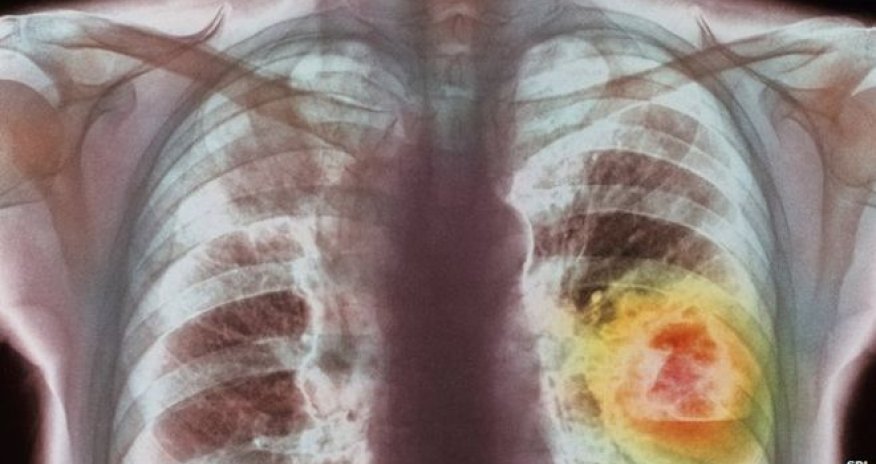

New cancer strategy 'could save thousands'

About 5,000 lives could be saved each year in England if GPs follow new guidelines on cancer diagnosis, the health watchdog NICE says.

But according to experts from the National Institute of Health and Care Excellence (NICE), although the situation is improving, thousands of lives are lost each year because tumours are being diagnosed too late.